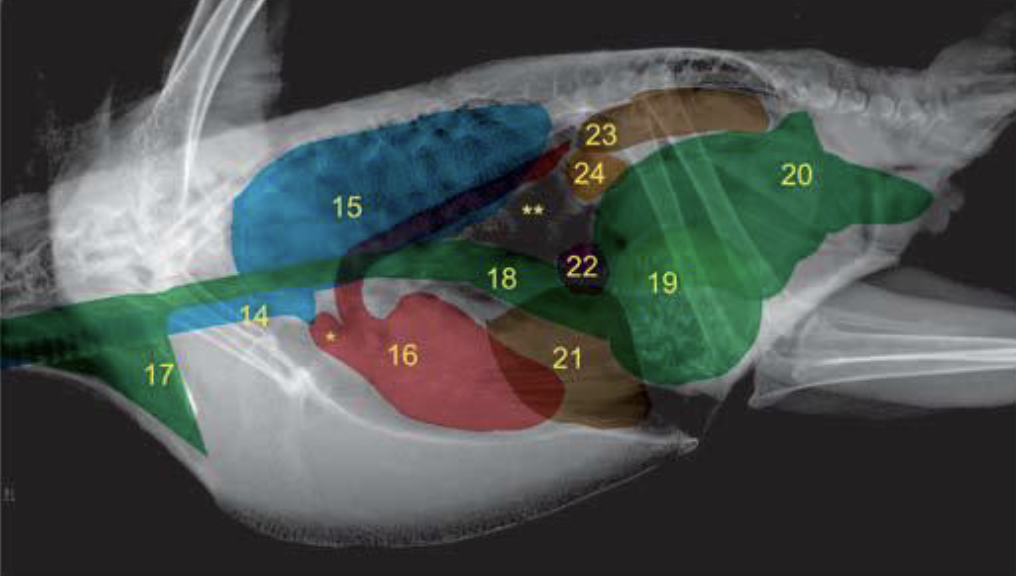

What are the anatomical structures labelled in this image?

A

19: intestines

17: liver

14: thoracic and abdominal air sacs

16: heart

15: diverticula; clavicular air sacs

20: cloaca

13: lung

18: ventriculus

15: lung

18: proventriculus

21: liver

14: trachea

23: kidney

22: spleen

17: crop

24: gonad

19: ventriculus